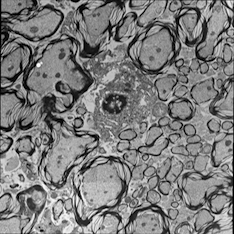

For image analogies based image registration, I have corresponding TEM/Confocal Microscopic image pairs of mouse brains with corresponding regions highlighted by a box. Using the correlative microscopy technique on the mouse brain, I want to localize specific brain regions associated with Pelizaeus-Merzbacher Disease (PMD) and do quantitative assessment of hypomyelination and demyelination in mice. PMD is one of a group of genetic disorders characterized by progressive degeneration of the white matter of the brain affecting the myelin sheath, the fatty covering that acts as an insulator on nerve fibers in the central nervous system.

The confocal microscopy images are multichannel color images in our test dataset. The blue channel is based on the blue stain DAPI (a fluorescent stain) which stains the DNA of the cell nucleus and corresponds to dark regions within the nuclei in the TEM. The green channel is based on the stains of the myelin sheats, visible as dark black layers covering the neurons in the TEM images. The red channel is not explicitly stained for and is caused by the auto-fluorescent effect of lipofuscin. The confocal image with RGB channels and its corresponding TEM image are shown in Fig. 5.

Currently I have six pairs of 2D TEM/confocal images with resolutions 582.24 pixels per μm𝜇𝑚\mu m and 7.5887.5887.588 pixels per μm𝜇𝑚\mu m respectively (1μm=1micron=106m1𝜇𝑚1𝑚𝑖𝑐𝑟𝑜𝑛superscript106𝑚1\,\mu m=1\,micron=10^{-6}\,m). The resolution is different between two images and only a small region in the confocal image corresponds to the TEM image.

5.3 Image Analogies based Image Registration

5.3.1 Pre-processing

In the pre-processing step, I extract the corresponding region of the confocal image and resample both confocal and TEM images to an intermediate resolution. The final resolution is 14.52 pixels per μm𝜇𝑚\mu m, and the image size is about 200×200200200200\times 200 pixels, which is dependent on the original TEM image size.

From the example in Fig. 5, the blue and red channels are too noisy and contain less information compared to the green channel. We use only the green channel as grayscale image for the registration in our application. The datasets are roughly registered based on manually labeled landmarks with a similarity transformation model.

Refer to caption

(a) Red channel of confocal image

(b) Green channel of confocal image

(c) Blue channel of confocal image

(d) Grayscale of confocal image

(e) Confocal image

(f) TEM image

Figure 5: Example of Confocal image with RGB channels and TEM image